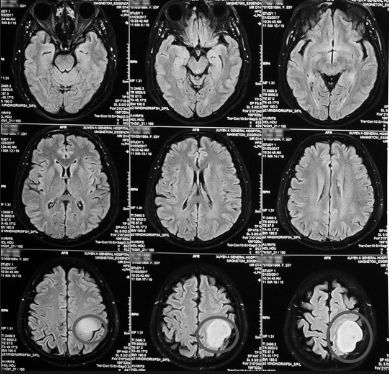

hình ảnh khối u não

hình ảnh U não